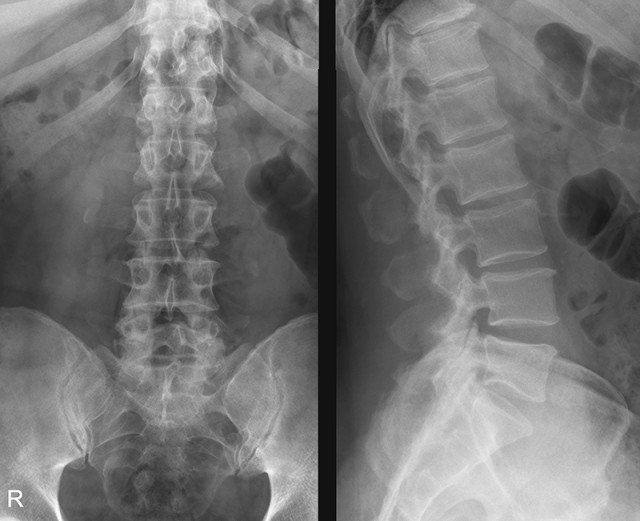

Прежде всего, стоит назвать его основное отличие от рентгеноскопии. Наука не стоит на месте, в том числе и медицинская, старые технологии устаревают, а на смену им приходят новые. Проблема в том, что рентген, как метод диагностики, давно и безнадежно устарел. Он используется по инерции, «по старинке» и совершенно не показывает таких результатов как УЗИ, притом, что вреда от рентгена (хоть и опосредованно) может быть больше.

Рентген как метод обследования устарел и уступает УЗ-диагностике

Кстати. При прохождении рентгенологического исследования пациент помещается между фотопленкой, на которой проецируется изображение, и источником излучения, проводящим волны сквозь человеческое тело.

В результате рентгена образуется черно-белая картинка, которая позволяет увидеть довольно мелкую детализацию, но радиационное облучение при этом попадает прямо в человеческий организм. И доза его варьируется в зависимости от того, какой по площади участок тела необходимо диагностировать. Позвоночник обычно занимает большую площадь, поскольку редко исследуется одна его зона, обычно облучению подвергаются как минимум две (например, шейно-грудная или пояснично-крестцовая). Поэтому рентген нельзя делать беременным и тем, кто кормит грудью, а также имеющим почечную недостаточность пациентам. Способ с применением ультразвука не имеет таких противопоказаний и ограничений.